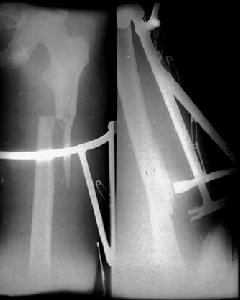

(三)切開復位和內固定 適用於復位不理想或斷端間有軟組織嵌夾,或有血管神經禹傷者可作切開復位。固定方法可用髓內釘或鋼板螺絲釘,同時,適當考慮套用外固定,要求達到固定確實可靠的原則。

(1)股骨上1/3或中上1/3骨折多採用髓內針固定。此法具有術後不用外固定及早期下床活動的優點。過去用開放式打入髓內針的方法,近十年來已被X光電視機(XTV)控制下,僅在穿針處作小切口,不顯露骨折端的閉合穿針方法所代替。閉合法較開放損傷小,出血少,不破壞骨折端的血液供給,有利於骨折癒合。

(2)股骨中1/3或中下1/3骨折,傳統方法是採用6-8孔接骨板螺絲釘固定及髖人字石膏固定。目前多採用加壓鋼板活動。加壓鋼板有多種類型,60年代開始套用加壓器的加壓鋼板固定,其後出現自身加壓鋼板固定沿用至今。有關股骨幹骨折手術及內固定材料選擇,要嚴重掌握適應症,不可濫用。要力求手術成功,防止感染及骨折不癒合的發生。